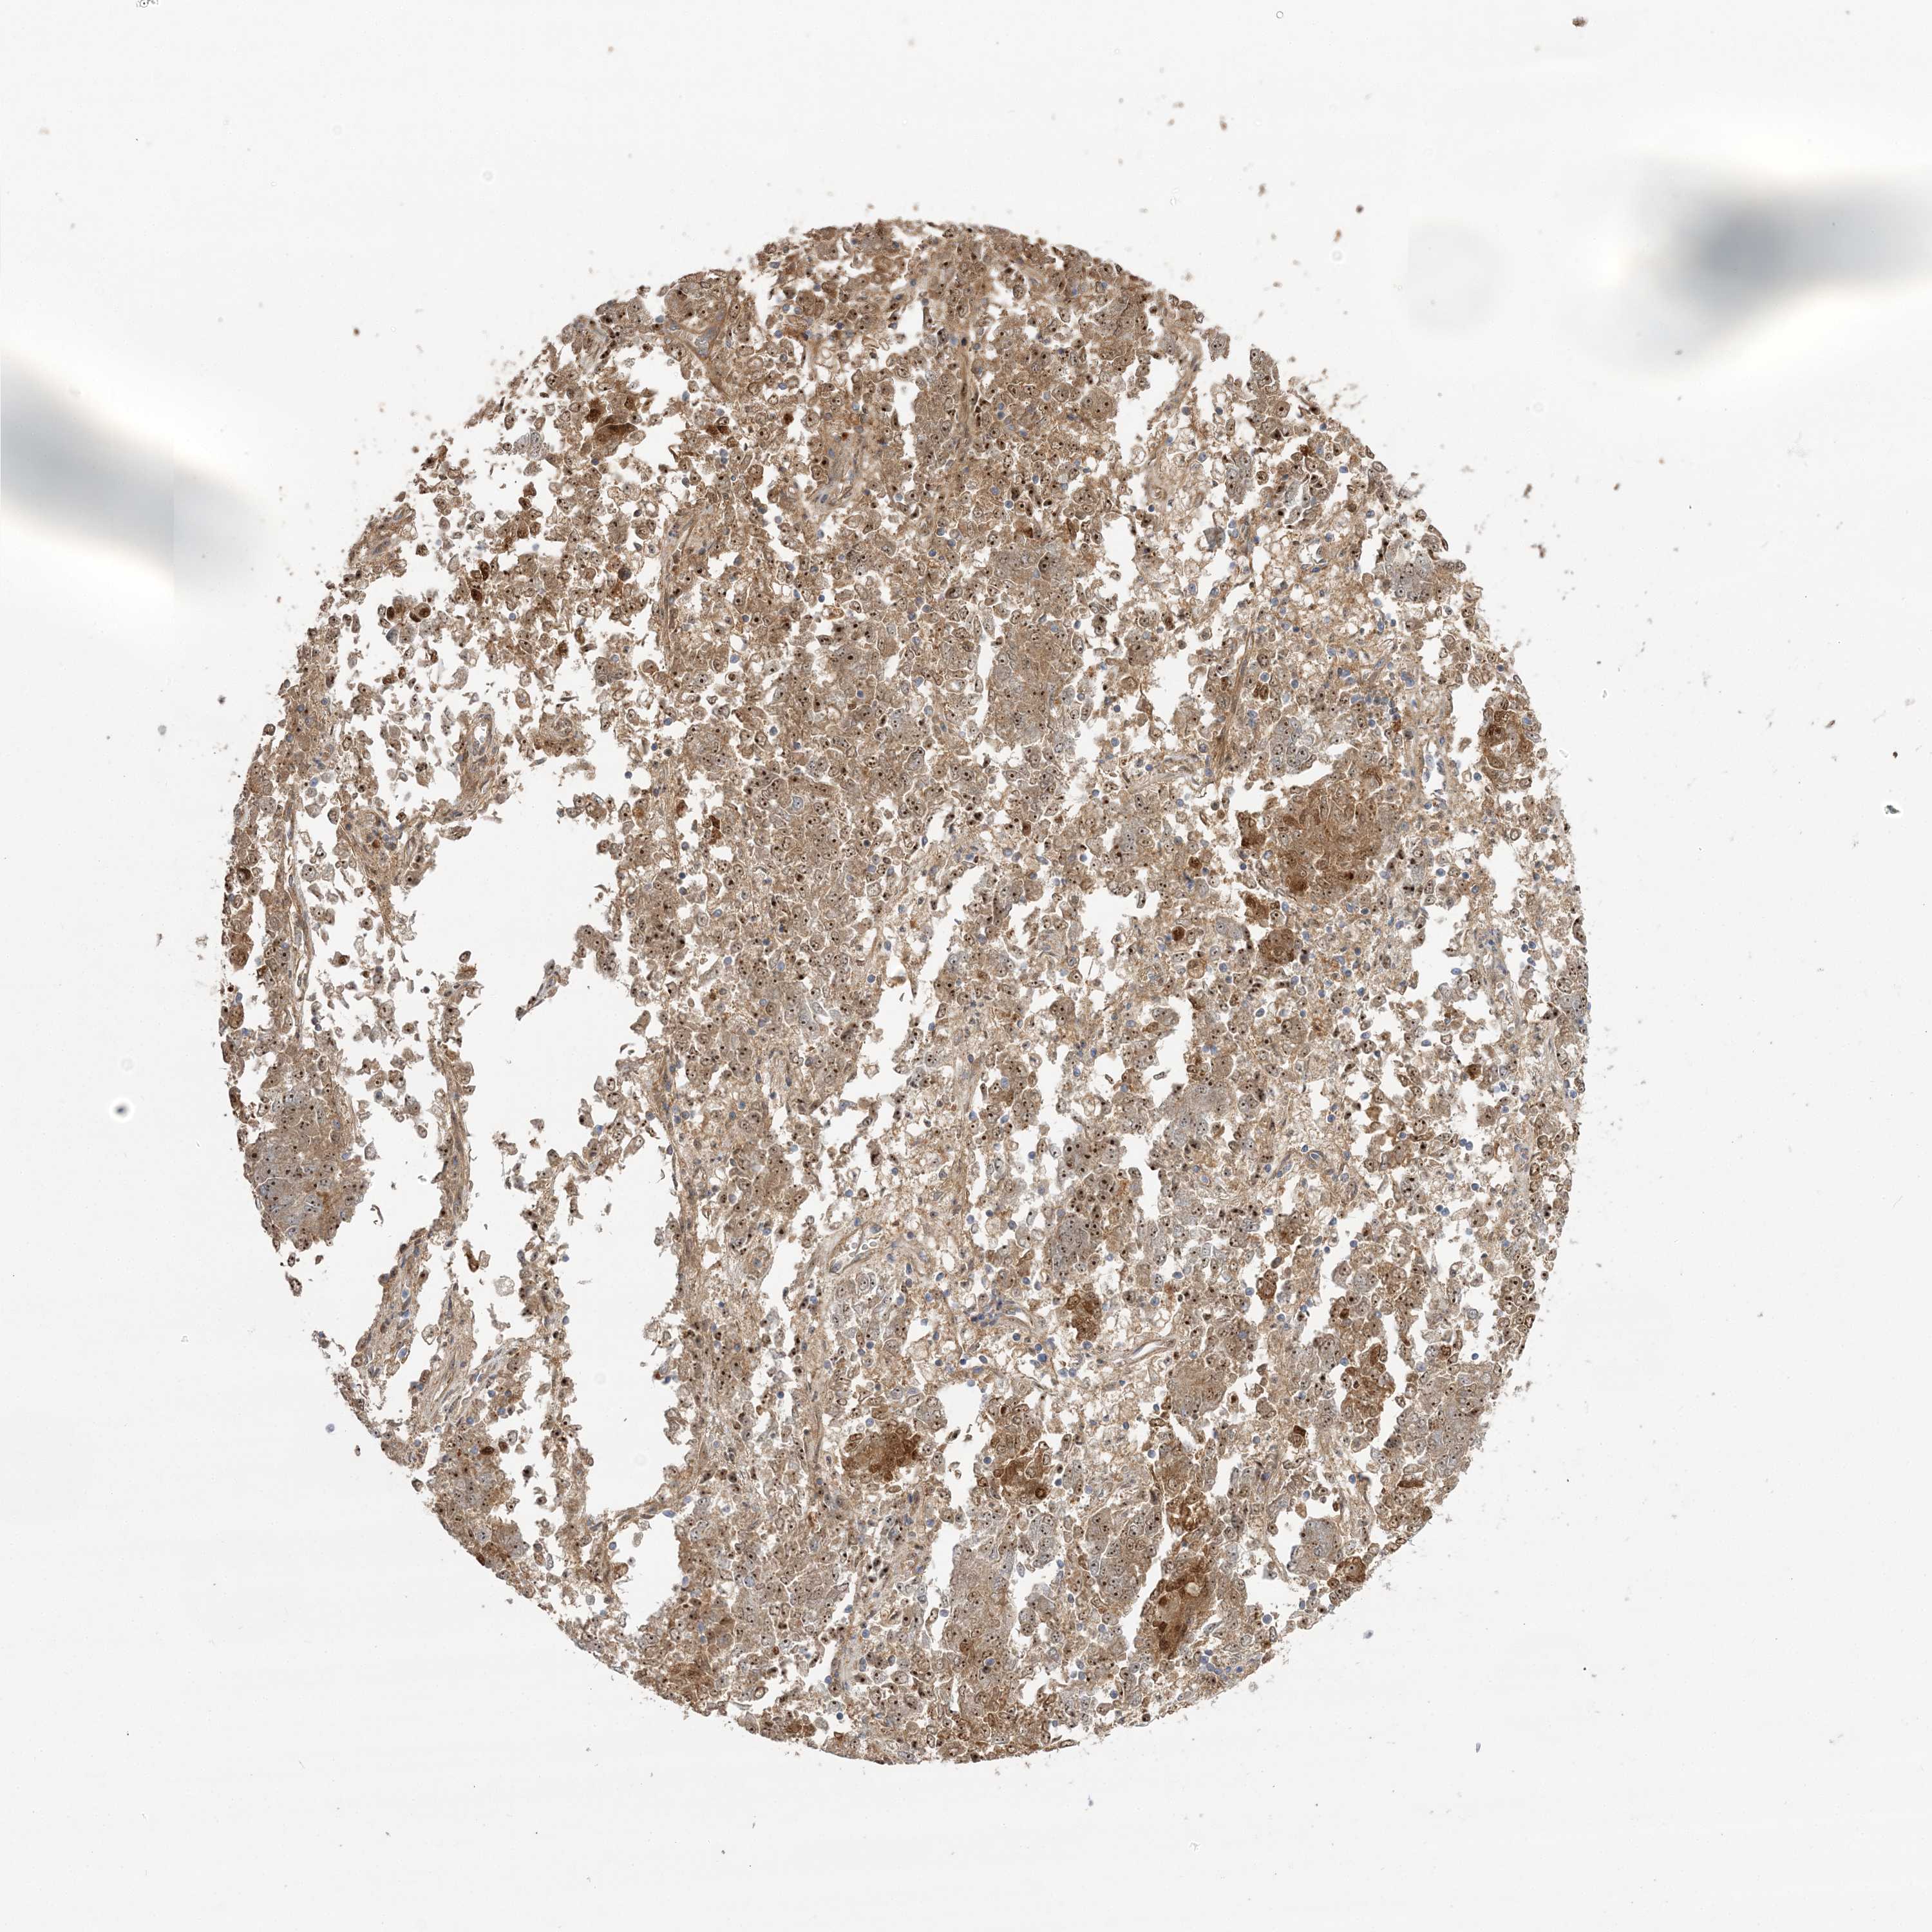

ENDOMETRIAL CANCER - Protein expressioni

A mouse-over function shows sample information and annotation data. Click on an image to view it in a full screen mode. Samples can be filtered based on level of antibody staining by selecting one or several of the following categories: high, medium, low and not detected. The assay and annotation is described here.

Note that samples used for immunohistochemistry by the Human Protein Atlas do not correspond to samples in the TCGA dataset.

Antibody stainingi

Antibody staining in the annotated cell types in the current human tissue is reported as not detected, low, medium, or high, based on conventional immunohistochemistry profiling in selected tissues. This score is based on the combination of the staining intensity and fraction of stained cells.

Each image is clickable and will lead to virtual microscopy that enables deeper exploration of all samples and also displays staining intensity scores, fraction scores and subcellular localization as well as patient and tissue information for each sample.

Antibody HPA036295

Antibody HPA036296

Staining

High

Medium

Low

Not detected

Intensity

Strong

Moderate

Weak

Negative

Quantity

>75%

75%-25%

<25%

None

Location

Nuclear

Cytoplasmic/membranous

Cytoplasmic/membranous,nuclear

Adenocarcinoma, NOS

Adenocarcinoma, metastatic, NOS